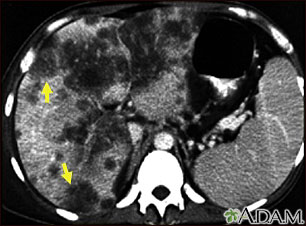

- CT scan of the abdomen